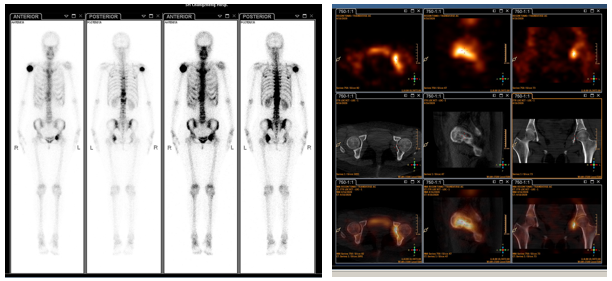

2020年8月31日,患者骨扫描示:右侧肱骨上段、左侧髋臼及胸腰椎体多发骨转移。

图6. 2020年8月31日的骨扫描结果